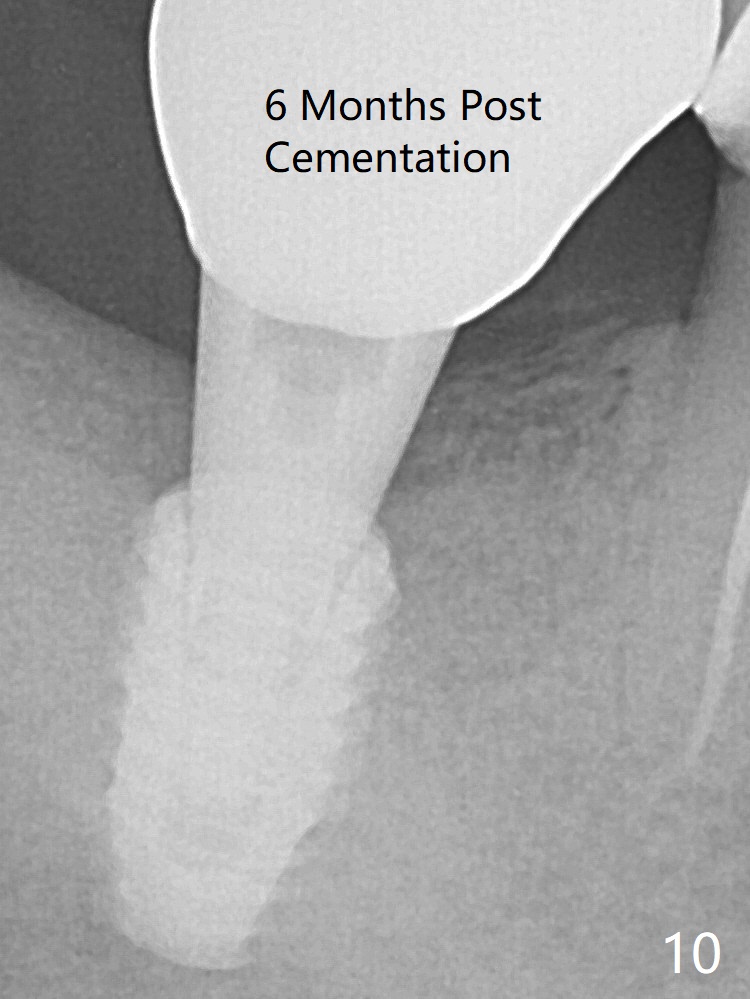

A 5x8.5 mm implant achieved primary stability in the final 1-2 mm. The implant was then placed ~ .5 mm deeper (~ 40 Ncm) (Fig.1). The implant, apparently having been osteointegrated 5.5 months postop (Fig.3), was placed deep, probably related to pressing the distal end of the guide too heavily. It is difficult to restore with use of a 5.2x5.5(5) mm abutment. There is apical bone loss (arrowheads), most likely due to the dense bone and heat during osteotomy. Immediately post cementation PA confirms the implant distal placement (Fig.6). The trajectory is not right, since no matter how the sensors are placed, the implant threads cannot be shown clearly (Fig.10), in consistence with the distolingual access hole (Fig.11).